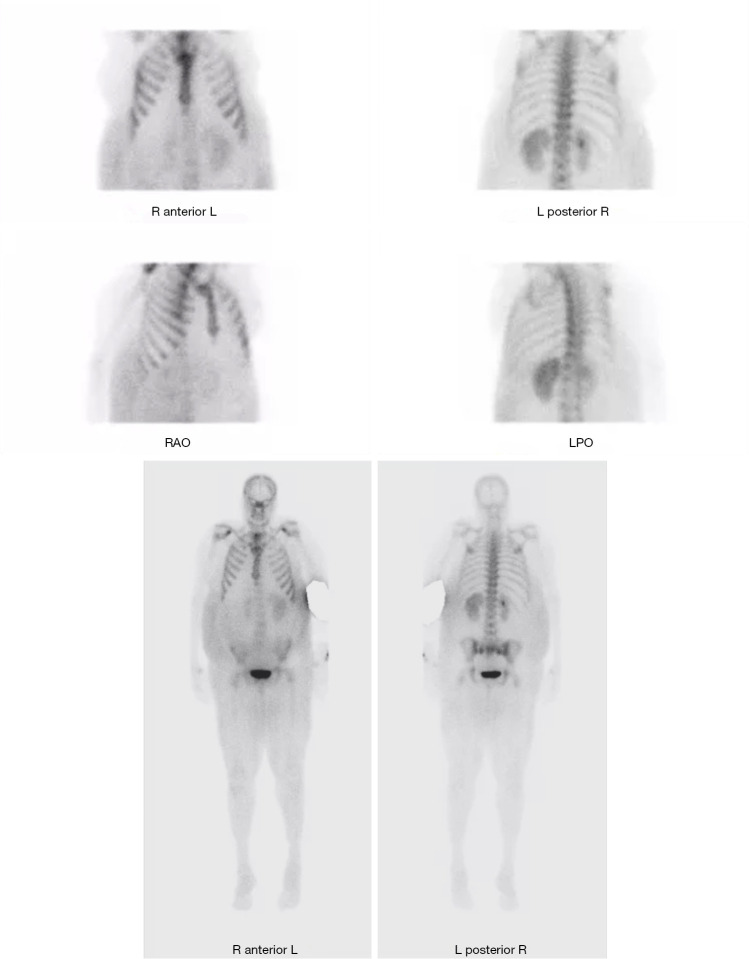

Case description: We present a rare case of HHM secondary to cholangiocarcinoma. This case presents a rare case of HHM due to cholangiocarcinoma with an atypical presentation in a 55-year-old female. This patient presented with abdominal swelling and severe hypercalcemia prompting evaluation for a possible gastrointestinal source and was found to have HHM due to cholangiocarcinoma. She was treated for her hypercalcemia medically, however due to the extent of her disease she was unable to undergo surgery. Chemotherapy was not considered during her initial presentation as she originally had a malignancy of unknown primary. Ultimately, shortly after her initial presentation, the patient passed at another hospitalization 36 days after her initial presentation.